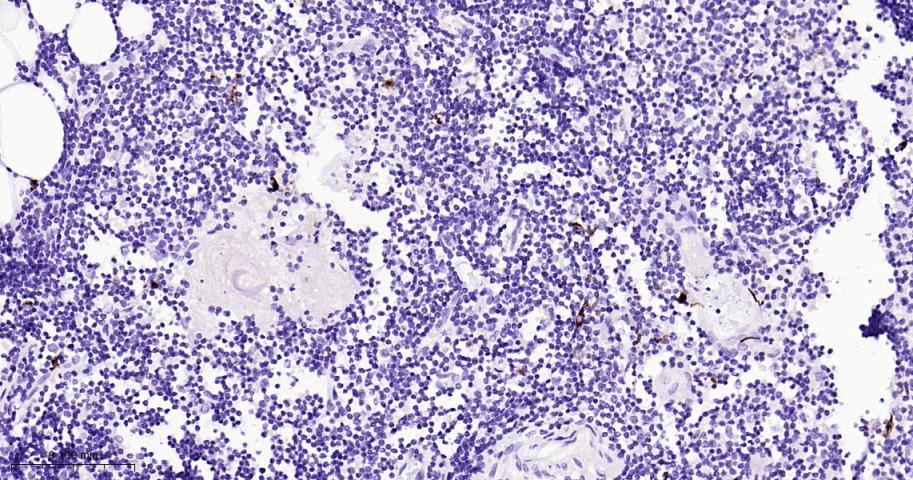

Paraformaldehyde-fixed, paraffin embedded Human Thymus; Antigen retrieval by boiling in sodium citrate buffer (pH6.0) for 15 min; Antibody incubation with CD207 Monoclonal Antibody, Unconjugated(bsm-61646R) at 1:200 overnight at 4°C, followed by conjugation to the bs-0295G-HRP and DAB (C-0010) staining.